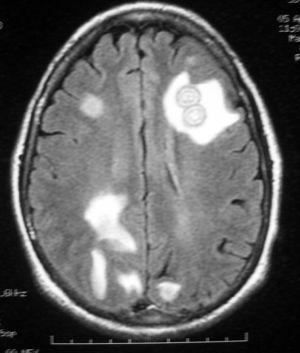

Figura 2.

Mujer de 60 años con uveítis crónica en tratamiento con corticoides. Ingresa por cuadro de tres días con cefalea, vómitos y fiebre, disminución del nivel de conciencia y disfasia. Al ingreso presentaba una temperatura de 39 ºC, crisis tónico clónicas y flúter auricular con hipotensión. Se intubó y conectó a ventilación mecánica. Se le realizó tomografía computarizada craneal con contraste y resonancia magnética donde se ven múltiples lesiones en ambos hemisferios cerebrales y en el cerebelo con captación en anillo (figs. 1 y 2) y edema asociado, que brillan en difusión, compatibles con abscesos piógenos. No se aisló ningún germen en sangre, orina, aspirado traqueal ni líquido cefalorraquídeo. Se realizaron estudios para encontrar el foco de la infección, exploraciones del área otorrinolaringológica, fondo de ojo, ecocardiografía transesofágica, etc., siendo todos normales. Tras tratamiento con meropenem la paciente evolucionó favorablemente, siendo dada de alta asintomática al Servicio de Neurología.